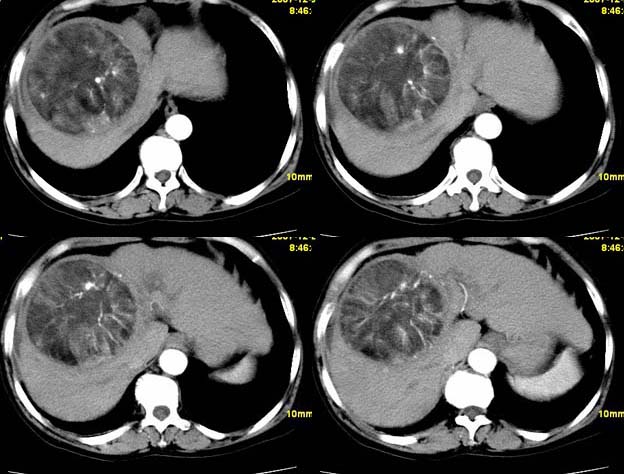

增强

肝血管平滑肌瘤脂肪瘤可能性大。

支持肝血管平滑肌脂肪瘤可能性大。

考虑1肝细胞腺瘤可能性大(病灶周围有透明环影)恶变?2血管平滑肌脂肪瘤?建议穿刺病检.

支持;肝aml-------脂肪成分,中心血管征,延时强化.